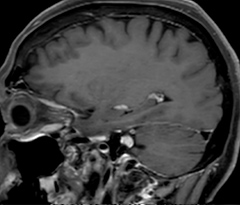

In this patient with acute right motor deficit and aphasia, the b2000 diffusion weighted image is normal. The SWIp image demonstrates more prominent veins in the right hemisphere, which could reflect increased deoxyhemoglobin contents. Fast ASL shows low CBF regions in the left frontal lobe. A follow-up ASL after one hour demonstrates high CBF values in the same area. The final diagnosis was migraine with aura.